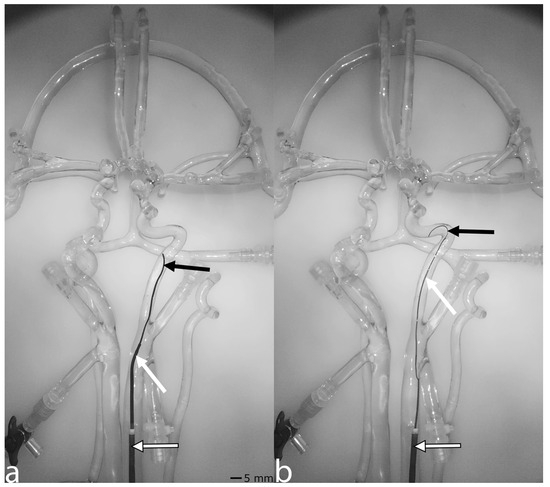

To enhance vessel and device visibility, as well as the overall visual experience, the fluoroscopy mode converts the camera signal to grayscale, rotates it by 90 degrees to replicate the orientation of an angiography unit, and displays the result in real time. The model’s clear silicone vessels naturally allow for the visualization of vessels and endovascular devices. Figure 2a illustrates the fluoroscopy simulation with a balloon catheter, guiding catheter, and guide wire, while Figure 2b shows a balloon catheter, microcatheter, and microwire.

Figure 2. Fluoroscopy mode. The left panel (a) displays a balloon catheter, marked by a white arrow with black borders, along with a guiding catheter and guide wire, indicated by a white arrow and a black arrow, respectively, positioned within the left carotid artery. The right panel (b) shows a balloon catheter, also marked by a white arrow with black borders, alongside a microcatheter and microwire, indicated by a white arrow and a black arrow, respectively.

While AngioSim adequately displays catheters and guidewires sufficiently, 24% of participants still considered the simulation unrealistic, underscoring the need for further improvements. Future enhancements should focus on controlling the camera via a joystick, enabling camera rotation around the silicone model and incorporating a second camera for biplanar imaging. However, these upgrades may not fully resolve the issue of overlapping vascular structures, as the system relies on light-based imaging instead of the penetrating capabilities of radiation. Additionally, the grayscale display makes it challenging to distinguish between microcatheters and microwires without markers for ionizing radiation as depicted in Figure 2b and Figure 3d and to identify the exact position and orientation of other medical devices such as stent retrievers.